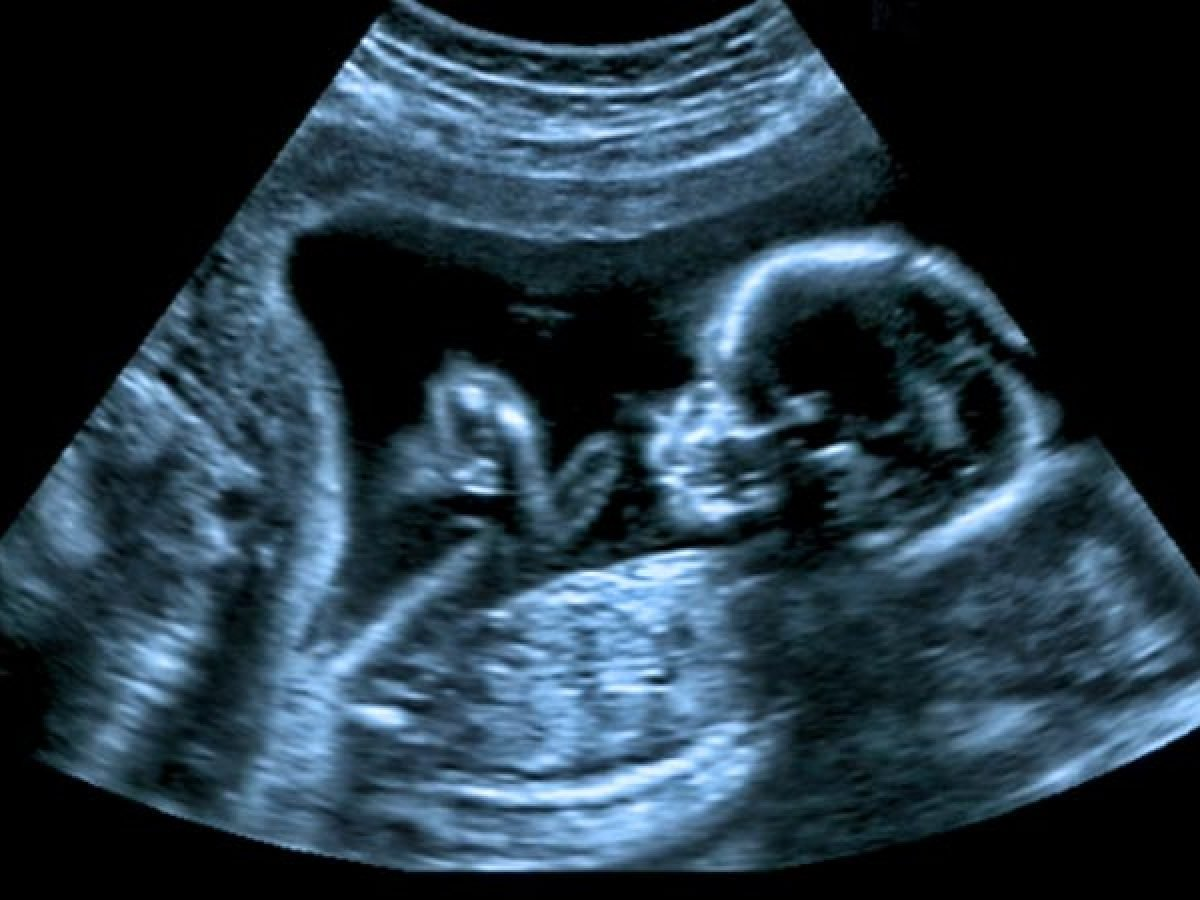

La sífilis congénita ocurre cuando una mujer con sífilis no tratada o tratada inadecuadamente transmite la infección a su bebé durante el embarazo o el parto. Está causada por la bacteria Treponema pallidum, que puede atravesar la placenta y afectar al feto desde etapas tempranas de la gestación.

Si no se detecta a tiempo, la infección puede provocar abortos espontáneos, partos prematuros, muerte fetal o complicaciones graves en el recién nacido, como lesiones en la piel, anemia, daño óseo, alteraciones neurológicas y sordera. Sin embargo, con diagnóstico prenatal y tratamiento con penicilina, la sífilis congénita puede prevenirse completamente.

El control prenatal y la detección temprana son fundamentales, ya que las mujeres gestantes infectadas suelen no presentar síntomas evidentes. Una sola dosis de penicilina benzatínica administrada oportunamente elimina el riesgo de transmisión al bebé y evita las complicaciones más graves.